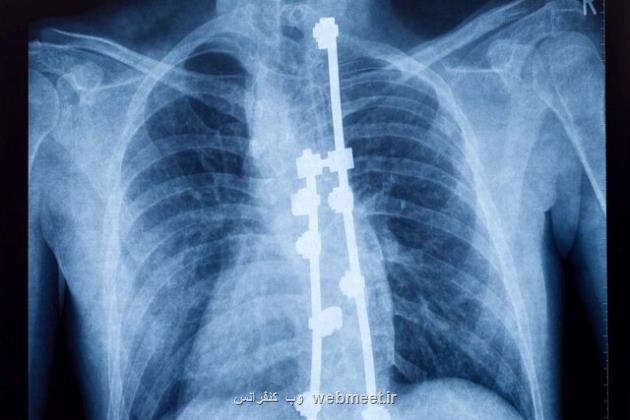

پژوهشگران دانشگاه کالیفرنیا در ریورساید از یک نوآوری رونمایی کرده اند که امکان تصویربرداری با وضوح بالا از نخاع انسان در حین جراحی را فراهم می آورد. آنها آنرا «تصویربرداری سونوگرافی کاربردی» (fUSI) می نامند.

این فناوری برای پزشکان دیدی از نخاع فراهم می آورد و همین طور نقشه برداری در لحظه از پاسخ طناب نخاعی به درمان های مختلف را ممکن می کند. این فناوری می تواند کاربردهای بی حد و حصری داشته باشد، خصوصاً برای کاهش درد میلیونها نفر در سرتاسر جهان که از کمردرد مزمن رنج می برند.

واسیلیوس کریستوپولوس (Vasileios Christopoulos)، استادیار مهندسی زیستی در دانشگاه کالیفرنیا ریورساید، پیشگام استفاده از «تصویربرداری سونوگرافی کاربردی» برای تصویربرداری از نخاع بود. برخلاف روش های سنتی مانند تصویربرداری رزونانس مغناطیسی عملکردی (fMRI)، «تصویربرداری سونوگرافی کاربردی» دارای تحرک قابل توجهی است. این سیستم نیاز به زیرساخت های گسترده ندارد و ابزاری همه کاره برای محیط های مختلف پزشکی است.

این بیماران که از درمان های دیگر تسکینی پیدا نکردند، تحت تحریک نخاع با الکترود قرار گرفتند. هدف کاهش ناراحتی آنها و افزایش کیفیت کلی زندگی آنها بود.